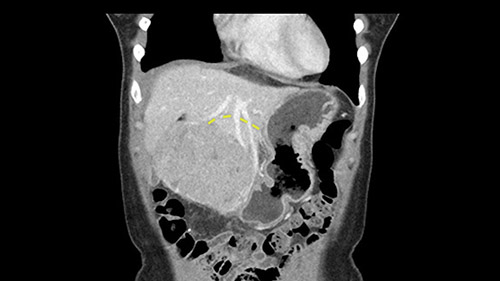

So if we look at the CT scan, on the axial, it’s a larger lesion. It’s about 6 or 7 or 8 centimeters. So it does look a bit threatening in terms of its resectability but if you really drill down deeply into the anatomy, and I think the coronal [imaging] is even better, you can see that the entire mass is on the patient’s left side of the falciform ligament. So it’s really only a left-sided tumor and not even really a left-sided tumor because Segment 4 is uninvolved anatomically.

As I review the CT scan, we have both arterial and venous phases, the tumor is obvious. But I’ll start by saying that the liver itself does not appear to be cirrhotic to my eye. It’s got a normal contour and allied to that, that I do not see evidence of portal hypertension. The spleen is normal, there’s no collateral vessels. The tumor itself, I measured maximally at about 11 centimetres in diameter and I’m told the alpha fetoprotein is very high (over 10000), which is entirely consistent with this being a solitary hepatocellular carcinoma that is very exophytic. It seems to emanate off the inferior margin of Segment 3 (because that’s the falciform). I’ll start by saying that this is not transplantable. The tumor exceeds our guidelines for transplantation, but it's likely resectable based on normal liver and no portal hypertension.

So the issue with regards to resection. A left sided tumor. I believe I can see the falciform ligament right here so we’re looking at a resection of Segments 2, 3 of the left lobe of the liver. The left portal vein is right there. I think we’ll be wiser to take the left portal vein and therefore get well into Segment 4 and do a left hemihepatectomy. Certainly, one does not need to take the middle hepatic vein; it’s miles from the tumor.

The other thing I would do in this case is to certainly to assess the coronal phase as we can see in the coronal phase, this tumor looks like it's growing from Segment 3, and again I don’t think there’s involvement of the right side of the liver or even on Segment 4.